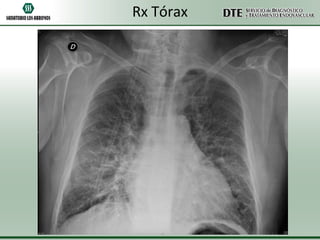

Rx Tórax